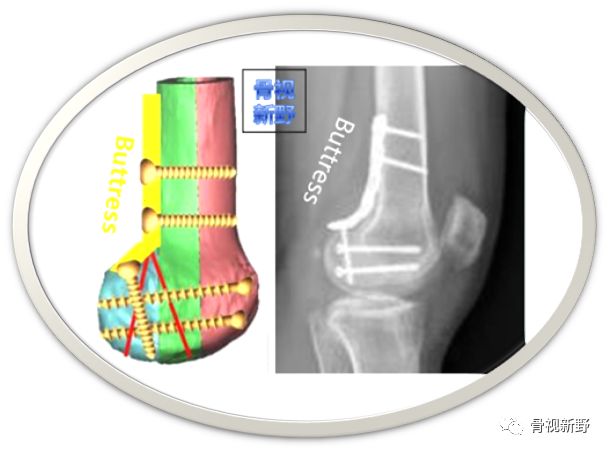

Buttress理念

由于Hoffa骨折存在较大垂直剪力,单纯螺钉固定失败病例报道较多。垂直剪力—单纯螺钉固定易导致骨折移位、固定失败:

Buttress固定理念

钢板-螺钉固定

在诸多螺钉固定失败的经验教训及在Buttress支理念支持下,各种拉力螺钉+钢板的组合应用均有报道,但总体以小直径拉力螺钉+小钢板支持或保护固定(后方/侧方)为主流趋势: